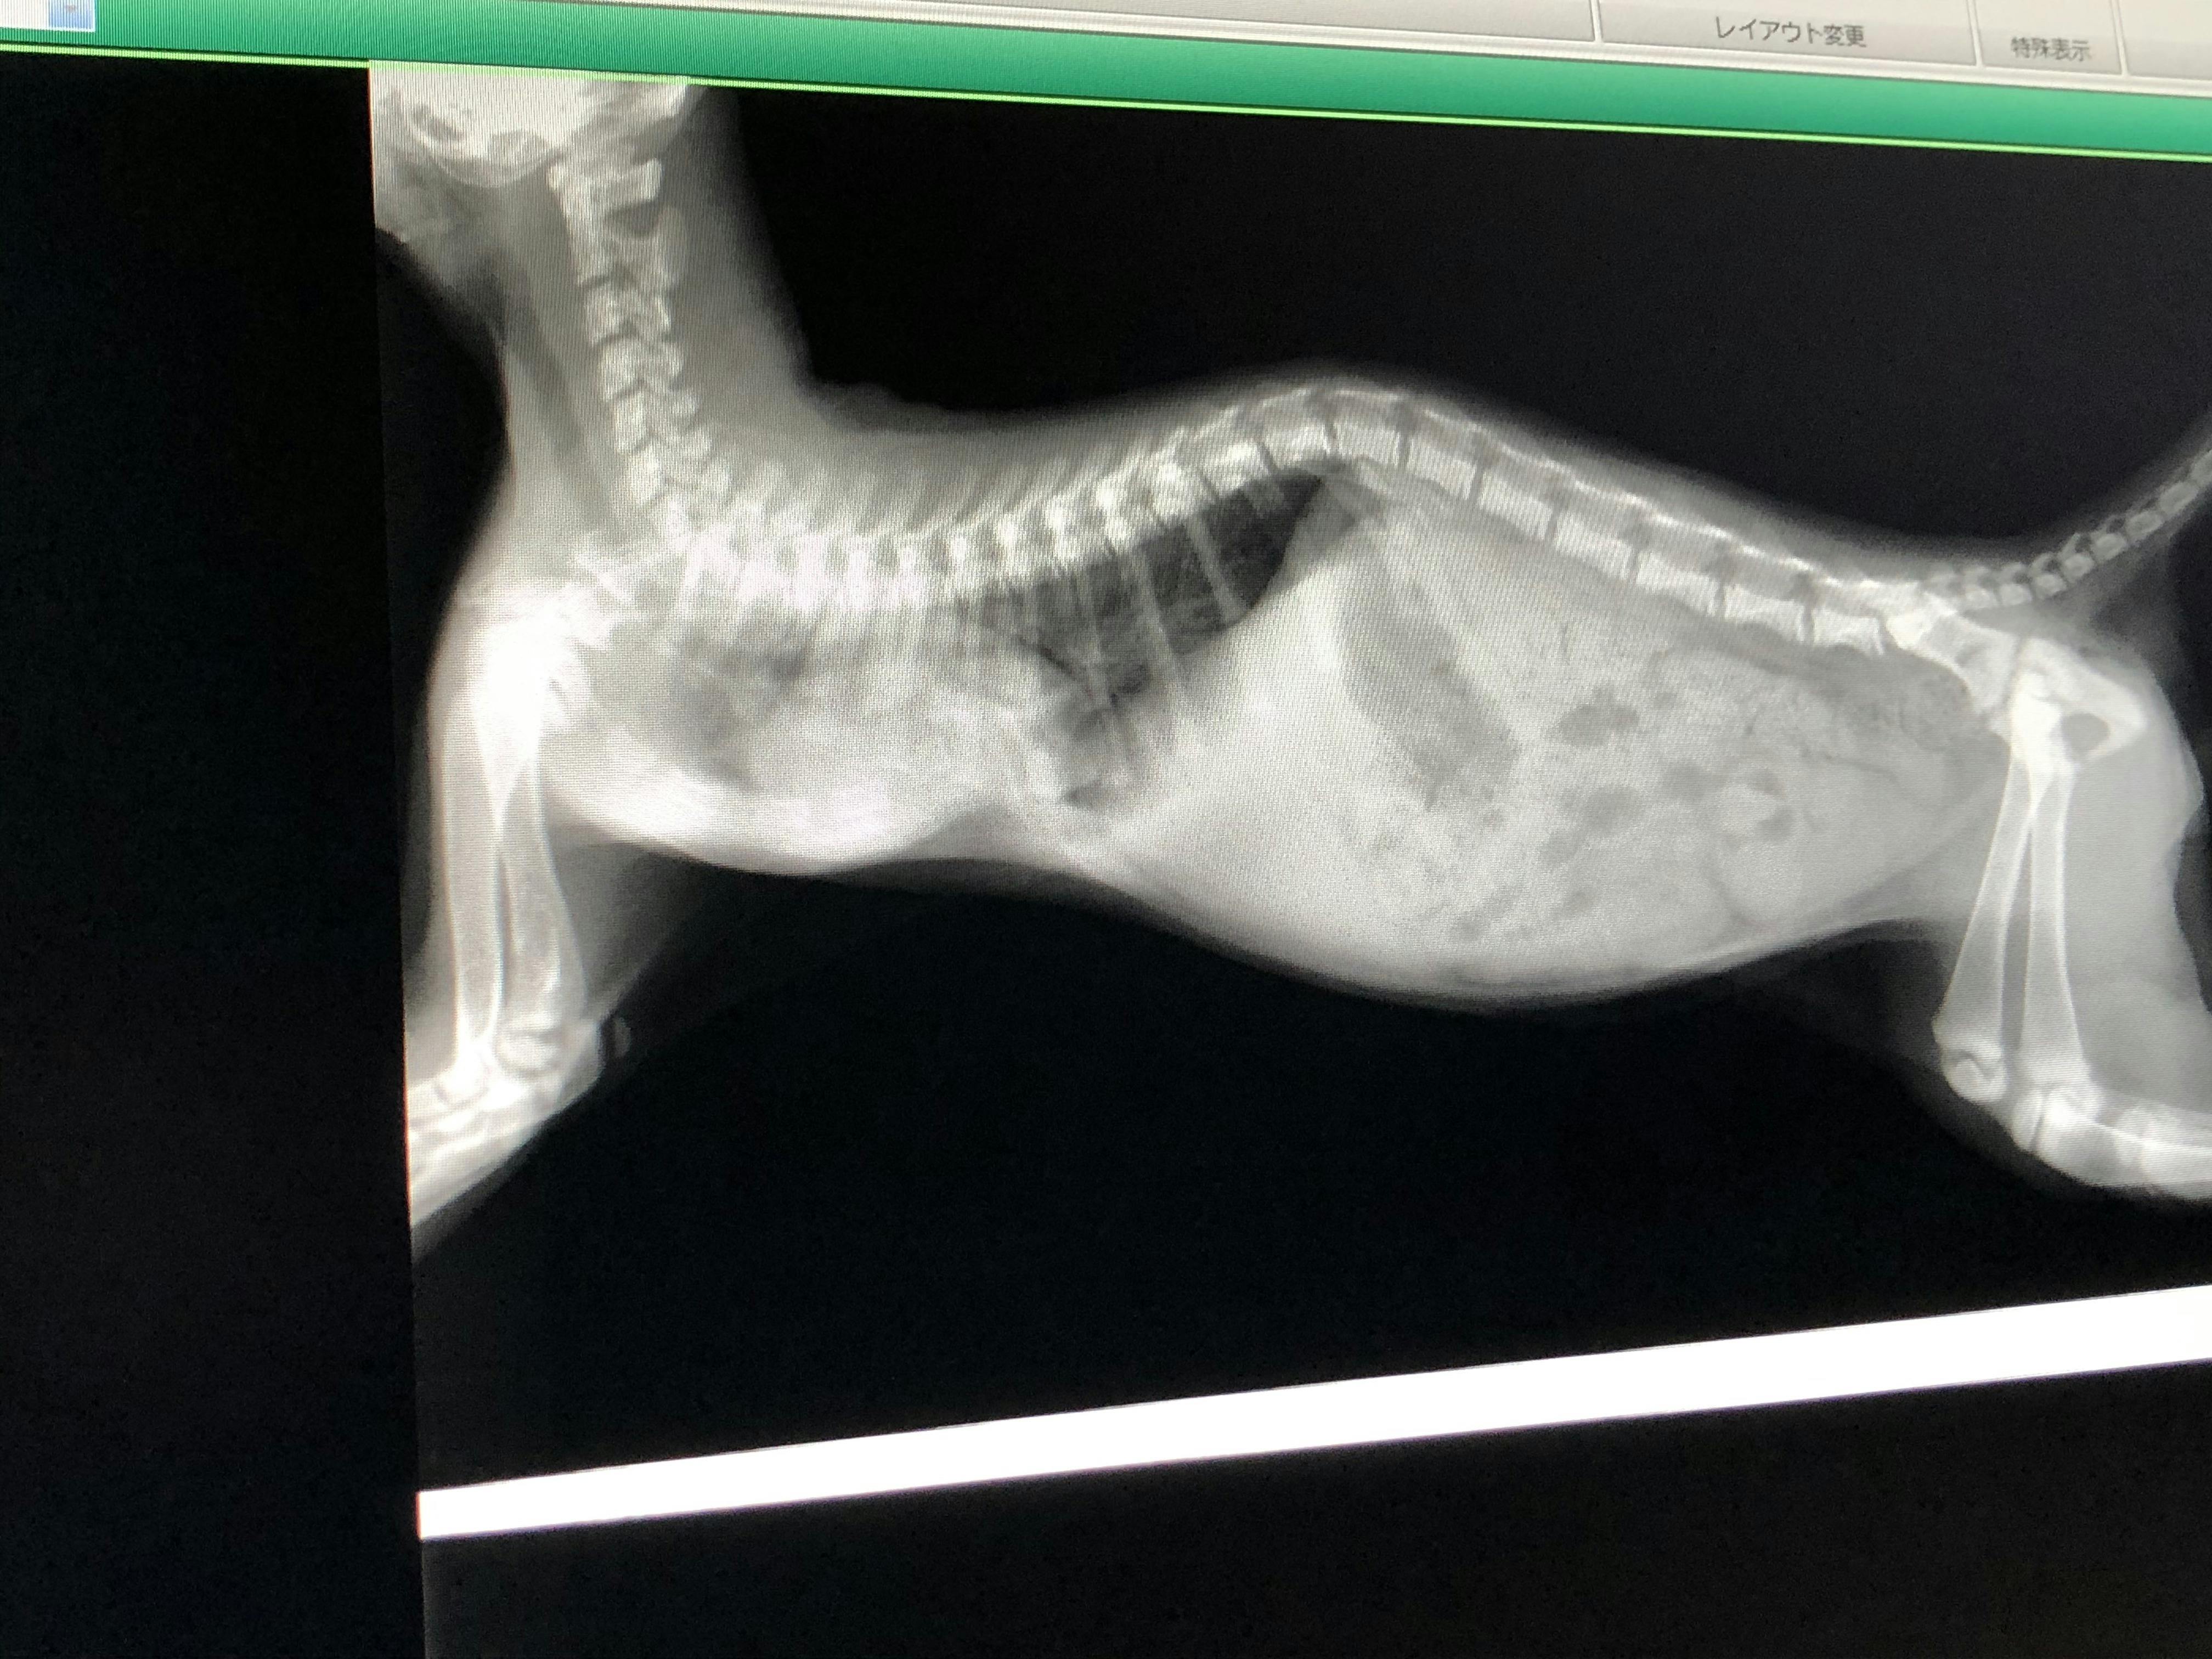

更にコロ助ちゃんは胸部肋骨が陥没している【漏斗胸】という病気を持っていました。

【漏斗胸】というのは遺伝性のある病気で、肋骨が心臓の方へ食い込んでしまい、呼吸が苦しくなってしまう病気です。

身体が成長しきる前にへこんだ胸骨を手術で引っ張る手術が必要ですが、手術に耐えるためには900gを超えなければ厳しいという診断だったので、預かりBABAさんが病気のせいもあって成長がとても遅いコロ助ちゃんに毎日せっせと高カロリー食を食べさせてくれて、ようやく手術に耐えられそうな体重になったので、先日最終検査をして2時間半を超える手術を乗り越えてくれました。

これがコロ助ちゃんの手術前と手術後のレントゲン写真です。

鋭角に食い込んでいた骨がほぼ平らになり、骨に阻害されていた心臓も本来の位置に近くなっています。

遊んでいても少し走るとすぐに口の中もお腹も紫色になりチアノーゼを起こしていたコロ助ちゃんですが、1ヶ月の安静という試練はあれどきっと元気になってくれると思います。